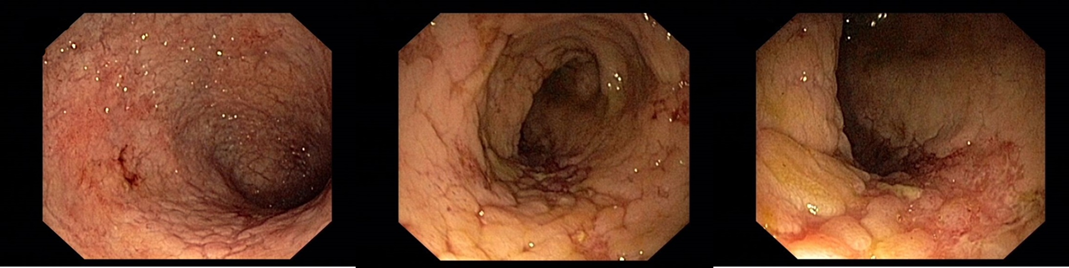

Koloskopie: edém, eroze, ulcerace, zánětlivé polypy v terénu po zánětlivých změn

018/2 Slizniční zhojení. Monoterapie vedolizumabem

Slizniční zhojení

Histologie: lehká porucha architektoniky krypt, může se jednat o pozánětlivé změny. Jiné histopatologické změny přítomny nejsou.